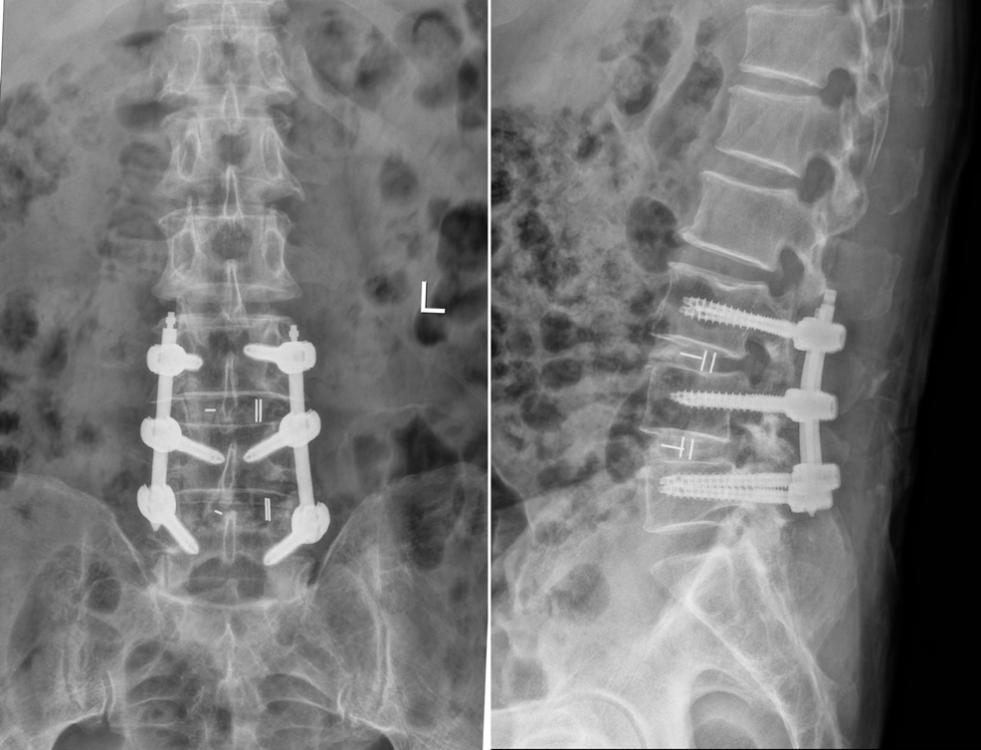

术后X线:腰椎滑脱复位,融合器横置恢复腰椎曲度